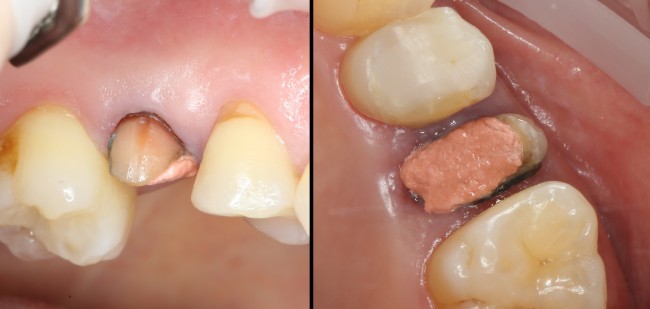

Вот исходная клиническая картинка:

К сожалению, попытка вылечить зуб эндодонтически и восстановить с помощью вкладки/коронки потерпела неудачу. Поэтому приходится его удалять.